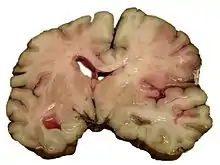

Intracerebral bleed

It generally occurs in small arteries or arterioles and is commonly due to hypertension,[49] intracranial vascular malformations (including cavernous angiomas or arteriovenous malformations), cerebral amyloid angiopathy, or infarcts into which secondary hemorrhage has occurred.[2] Other potential causes are trauma, bleeding disorders, amyloid angiopathy, illicit drug use (e.g., amphetamines or cocaine). The hematoma enlarges until pressure from surrounding tissue limits its growth, or until it decompresses by emptying into the ventricular system, CSF or the pial surface. A third of intracerebral bleed is into the brain's ventricles. ICH has a mortality rate of 44 percent after 30 days, higher than ischemic stroke or subarachnoid hemorrhage (which technically may also be classified as a type of stroke[2]).